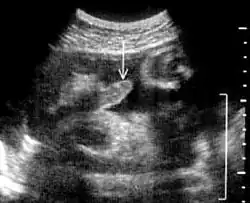

El pene bífido es una anomalía congénita; durante el desarrollo fetal en el útero, en un momento en los órganos genitales masculinos son morfológicamente en evolución, es decir, alrededor de la 6.ª semana de gestación, hay una fusión incompleta de lo que se conoce estructuralmente como el tubérculo genital, resultando en una duplicación bilateral del pene, o diphallia, y en este caso, acompañada por una hipospadias o acortamiento de la uretra, por lo que el acto de orinar suele ser muy difícil.[49]